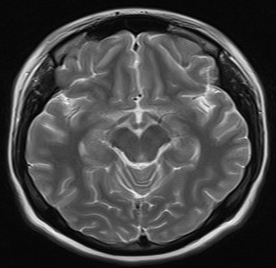

Four days later, magnetic resonance imaging (MRI) of the skull was performed, reporting brain parenchyma of both hemispheres, basal ganglia, thalamus, stem structure, and cerebellum of normal morphology and intensity (Figures 1 and 2). Likewise, an electroencephalogram (EEG) is performed during wakefulness and sleep, reporting within normal limits and observing epileptiform activity.

Figure 2 ThreeBrain MRI in sagittal section without evidence of intraparenchymal or structural lesions.